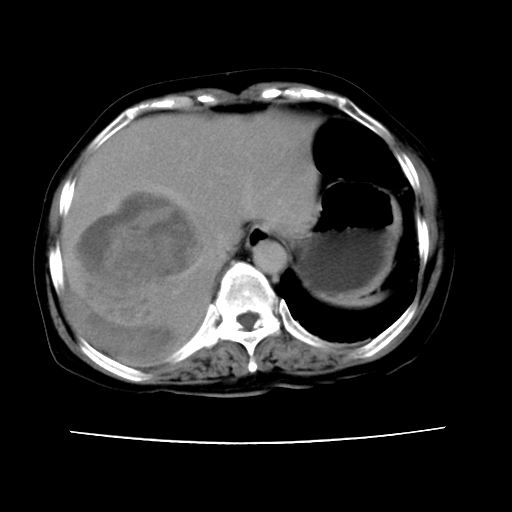

2008-11-10ct平扫(其间去中山医院诊治未行特殊治疗)

2008-11-10ct平扫见并肝内、血膜下血肿基本吸收,肝内低密度灶缩小。此时再做增强ct应有显着意义。对患者/医者都好!

从平扫+增强及治疗后复查片,病变明显缩小,不考虑肝癌出血可能,还是考虑为良性病变可能性大;单纯血肿并包膜下积液吧,病变强化没法解释,肝血管破裂出血吧,增强不符合典型血管瘤的表现,良性肿瘤破裂出血吧,复查片看来好像也不太支持(没做强化也不太好说)。本人还是考虑单纯肝内血肿并包膜下积液,强化是不是血管有外渗。

患者自6月至11月,如果是肝癌,没有经过特殊治疗,想必应该会有所进展吧,而不是ct所见,反而似有病灶减小的趋势。建议增强。

病变破裂出血应首先考虑,病变性质即可能是恶性也可能是良性,楼主说患者到上级医院检查未见癌细胞,以良性可能性大,首先考虑腺瘤破裂出血可能。

追问病史,患者有过度用力病史,当时立即感腹痛;所以还考虑肝破裂可能性大。